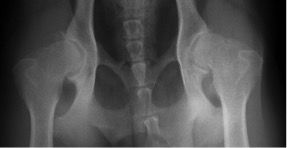

Für das PennHIP® Verfahren werden drei Röntgenaufnahmen angefertigt:

Bei der Distraktionsaufnahme wird ein sogenannter Distraktor zwischen die Beine des Tieres gelegt. Wenn der Untersucher die Beine des Hundes gegen den Distraktor drückt, wird der Oberschenkelkopf aus der Hüftpfanne „herausgezogen“. Je weiter das möglich ist, desto lockerer ist die Hüfte und desto größer die Wahrscheinlichkeit, dass ein Hund an einer HD leiden wird. Das Maß für die Lockerheit des Hüftgelenks ist dabei der Distraktionsindex (DI).

links: komprimiertes Hüftgelenk

rechts: distrahiertes Hüftgelenk